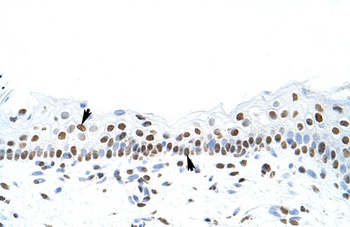

Antibody used in IHC on Human Intestine at 4.0-8.0 ug/ml.

Antibody used in IHC on Human Skin at 4.0-8.0 ug/ml.